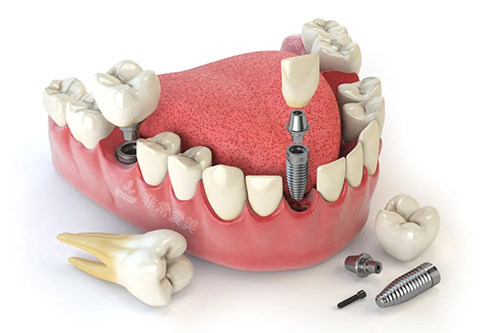

牙齿种植牙模型卡通示意图

问:丁珍华口腔的种牙技术如何?

答:丁珍华口腔的种牙技术堪称很棒。

该口腔机构拥有可靠的种植团队,医师们都经过系统的种植学培训,掌握了可靠的种植技术和理念。

在种牙前,会为患者进行超全的口腔检查和详细的诊断,制定个性化的种植方案。

他们使用的种植体都是经过严格筛选的优质产品,具有良好的生物相容性和稳定性。

在种植过程中,医师们操作比较准、熟练,能够将种植体更准地植入到牙槽骨内,大大提高了种植的可行性。

术后,还会为患者提供贴心的护理指导,帮助患者尽快修养。

许多在丁珍华口腔种牙的患者,都修养了正常的咀嚼功能,对种牙结果赞不绝口。